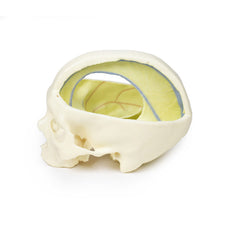

The head and neck of the specimen provides views of both superficial and deep structures in the region. The calotte has been removed ~2cm superior to the orbits to expose the brain in relation to the endocranial cavity. The transverse section through the cerebrum demonstrates the relation of the grey matter cortex to the white matter medulla, as well as the lateral ventricles with a small amount of choroid plexus visible in the base of both spaces. The skin and superficial fascia on the right side has been retained and false-coloured to display the angiosomes of the face and posterior neck. On the left side, the superficial tissues have been dissected to expose the muscles of facial expression, muscles of mastication, and deeper structures of the infratemporal fossa including the lingual nerve, terminal branches of the external carotid artery into the superficial temporal and maxillary arteries.

The head and neck of the specimen provides views of both superficial and deep structures in the region. The calotte has been removed ~2cm superior to the orbits to expose the brain in relation to the endocranial cavity. The transverse section through the cerebrum demonstrates the relation of the grey matter cortex to the white matter medulla, as well as the lateral ventricles with a small amount of choroid plexus visible in the base of both spaces. The skin and superficial fascia on the right side has been retained and false-coloured to display the angiosomes of the face and posterior neck. On the left side, the superficial tissues have been dissected to expose the muscles of facial expression, muscles of mastication, and deeper structures of the infratemporal fossa including the lingual nerve, terminal branches of the external carotid artery into the superficial temporal and maxillary arteries.